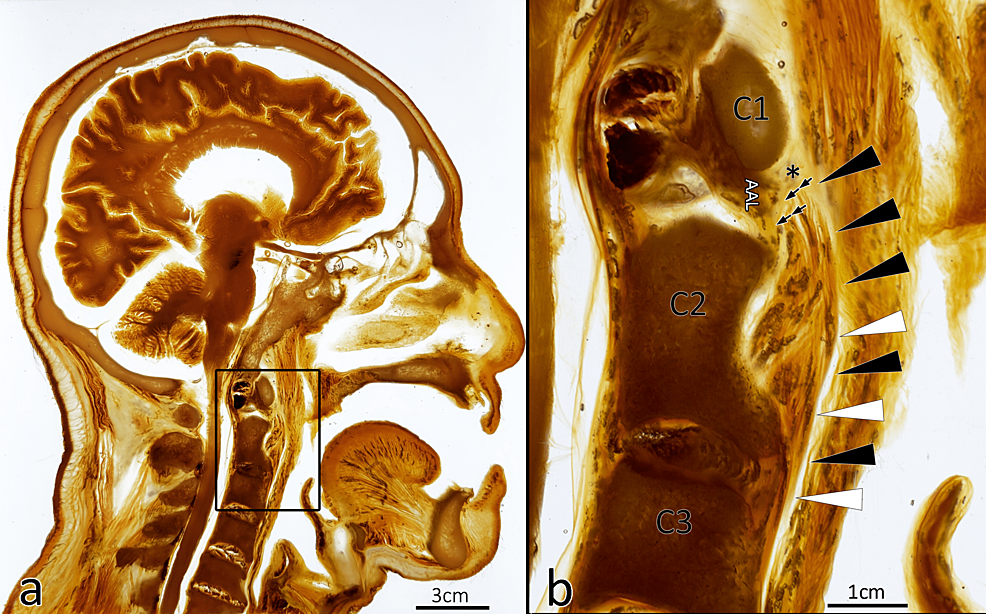

From www.cureus.com

Cureus The Alar Fascia and Danger Space A Modern Review Danger Space Fascia Two layers of fascia, superficial and deep, are commonly used to define the spaces of the neck. The superficial cervical fascia (scf). The danger space (alar space) is a deep compartment of the head and neck located posterior to the retropharyngeal space and. However, there are some diseases that are trans. A proper understanding of the anatomy, structure, function, and. Danger Space Fascia.